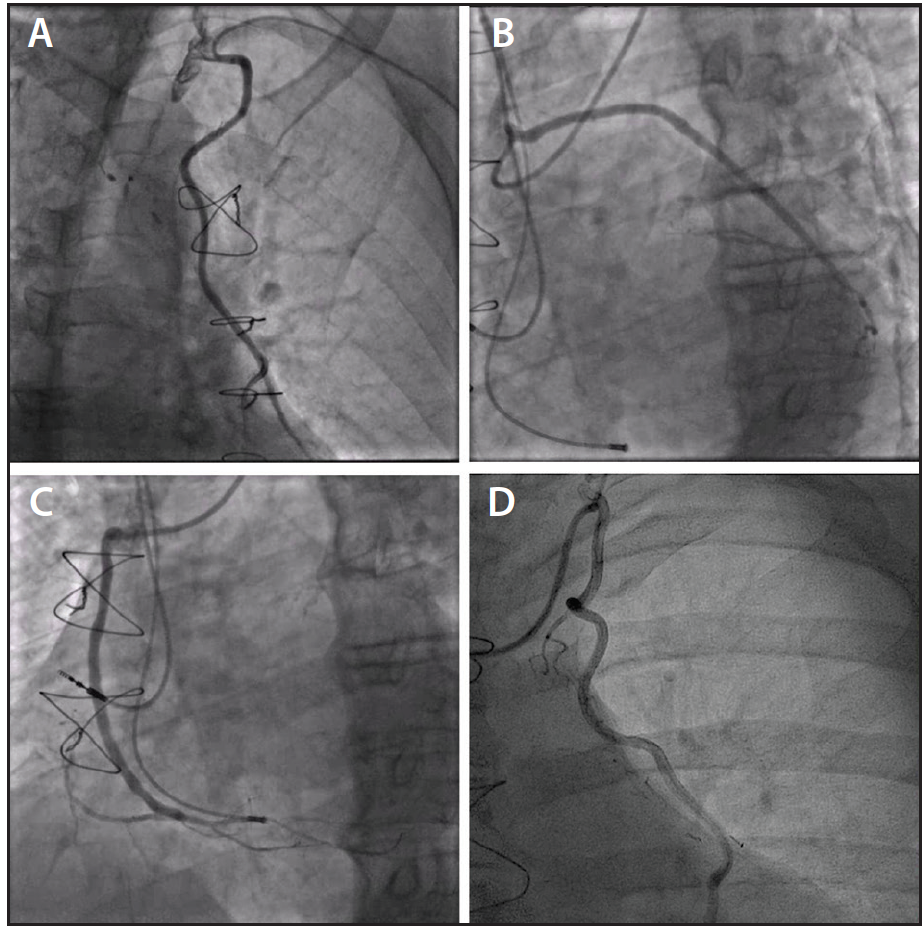

Figure 1. Engagement of the left internal thoracic artery with a Bartorelli-Cozzi catheter via a left radial approach (A). Engagement of a venous graft to the diagonal branch and obtuse marginal branch via a left radial approach (B). Engagement of a venous graft to the right coronary artery via a left radial approach (C). Engagement of the left internal thoracic artery with a mammary catheter via a right radial approach (D).

4. Different catheter shapes, both for diagnostic and guiding uses, should be available for left ITA cannulation from the left RA. These include Judkins right, Bartorelli-Cozzi (Figure 1A), internal mammary, and 3D RC (Williams) curves.

5. For diagnostic angiography, a Judkins right catheter is a reasonable first choice for both left and right venous grafts. However, better engagement and support for PCI can be achieved with multipurpose catheters for right grafts and with Amplatz left catheters for left grafts (Figure 1B and 1C).

When dealing with native coronary vessels, the right radial artery is by far the preferred approach because the operators are more comfortable given the usual setup of most angiographic suites, with the operator standing at the right side of the patient. However, the scenario is different in most CABG recipients because they have an in situ left ITA graft (usually to the left anterior descending coronary artery) and a variable number of aortocoronary venous grafts.12 In patients with a left ITA graft, the left radial artery should be the access of choice, because the ostium to the left ITA is straight on the way of the catheter path, and the engagement is easy, with good support in case of PCI. The engagement of the left ITA is also feasible using the right radial artery,13 but it requires complex catheter manipulation and is associated with poor catheter stability (Figure 1D). To engage the left ITA coming from a right RA, a left Judkins catheter is advanced in the aortic arch beyond the great vessels and is then slightly pulled back and rotated counterclockwise to point the tip of the catheter toward the origin of the left subclavian artery. Using an exchange-length hydrophilic wire, the subclavian artery is wired, and the left catheter is exchanged for a dedicated catheter to engage the ITA ostium. In the best hands, however, the rate of successful cannulation of the ITA is < 90%.